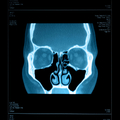

Гайморит это воспаление или инфекция придаточных пазух носа. Пазухи полости лицевой части черепа, и выстланы слизистой оболочкой. Гайморит это воспаление или инфекция этих пазух. Она развивается чаще всего в гайморовых пазух (под глазами) и решетчатой пазухи. В более серьезных инфекций инфекция может повлечь за собой кости (остеомиелита). Редко инфекция может распространиться на головной мозг и быть опасными для жизни.

ДИАГНОСТИКА

Изучение истории болезни и медицинский осмотр не проводятся. Порой КТ или МРТ будет сделано.

Медицинские процедуры, проводимые при заболевании гайморит (синусит): Спиральная компьютерная томографияЛЕЧЕНИЕ И ПРОФИЛАКТИКА